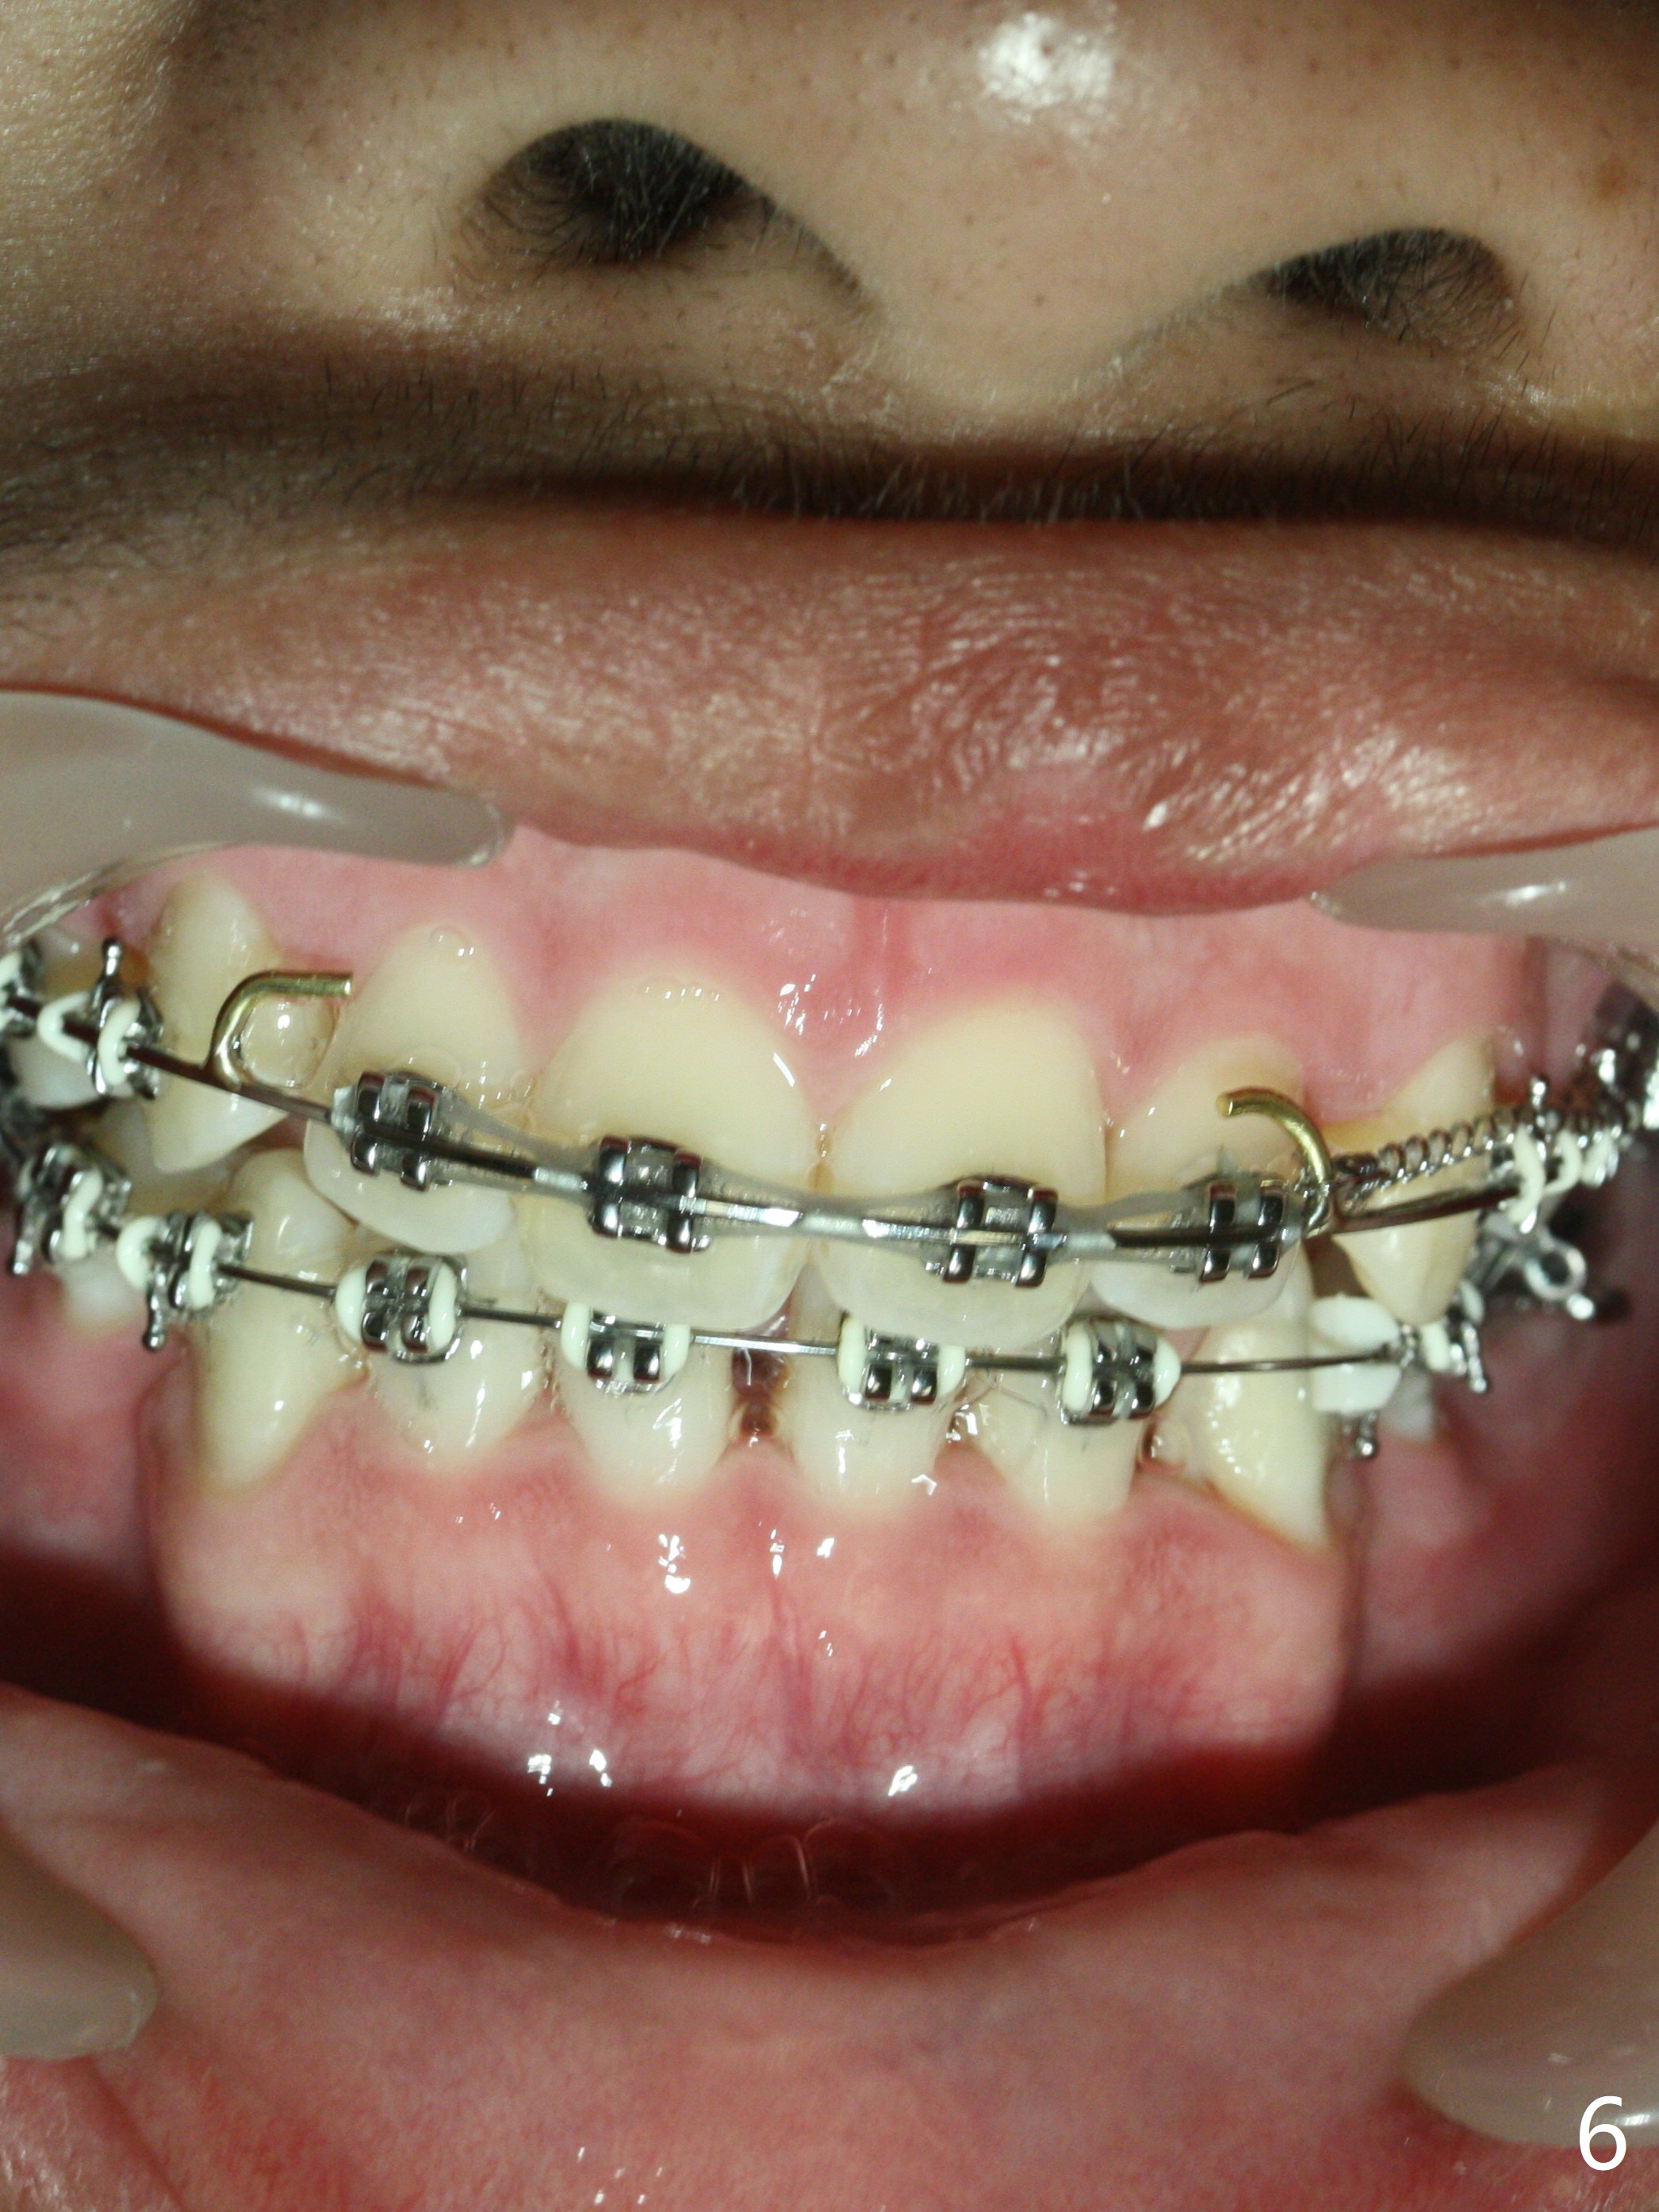

Twelve months post extraction and banding, there is anterior overjet. A posted wire is used to retract the upper incisors for a month. It appears that the upper midline deviates to the right (Fig.6, as compared to Fig.5 (pre-treatment)). Closed coil spring is removed on the right in hope that the upper midline will shift to the normal by the left coil spring (Fig.7-9). Is there a better alternative? There is mild root tip resorption 2 years 1 month post banding/immediate post debanding, as related to extraction ortho (Fig.10).